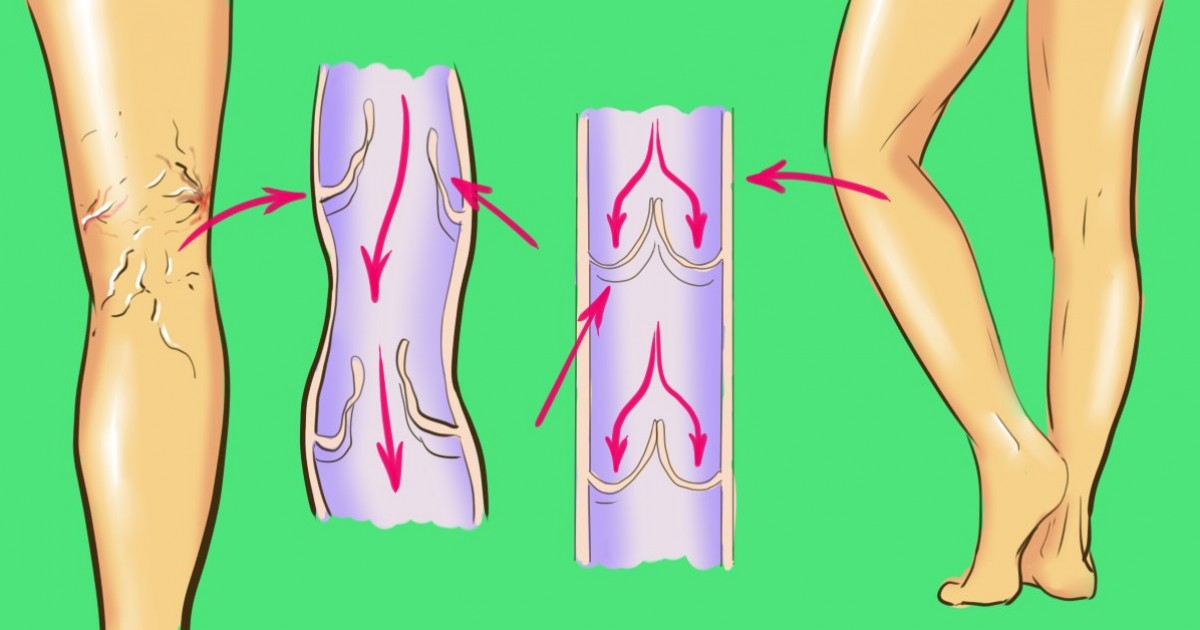

Beskrajna žudnja žena za lepotom (cipele sa visokim potpeticama, uskim pantalonama), hormonalni skokovi, naslednost i porođaj igraju okrutnu šalu sa lepšim polom. Malo po malo - i opa, proširene vene. I bez obzira na to koliko je ozbiljan tok bolesti, mnoge žene mogu rešiti problem bez operacije.